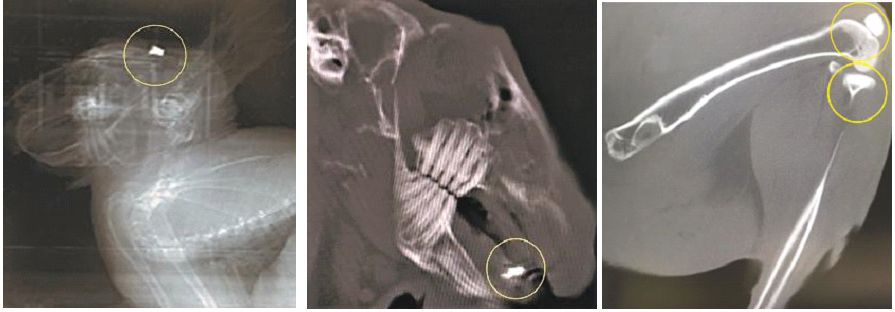

Созданы имплантаты, подобные натуральной кости

Ученые нашли способ создания биоматериалов из синтетических порошков и керамики на основе силиката кальция и его биологически активных композитов. Полученные из них имплантаты по структуре и свойствам подобны натуральной кости и могут стимулировать ее рост в организме человека. Статья об этом опубликована в журнале Progress in Natural Science: Materials International. Исследования поддержаны грантом Президентской программы исследовательских проектов Российского научного фонда.

Биоматериалы работают в непосредственном контакте с живыми тканями и клетками внутри организма. Наиболее крупные области их применения – производство медицинских имплантатов, в том числе костных. В качестве исходного сырья используются распространенные дешевые и доступные природные материалы, а технологии позволяют делать их биоактивными. Попадая в организм, такие системы взаимодействуют с костной тканью: стимулируют рост, способствуют миграции, делению и дифференцировке клеток.

К таким материалам существуют свои требования. Во-первых, они не должны оказывать отрицательного влияния на живые системы. Это главное условие, которое определяется химическим составом, свойствами поверхности и физическими показателями компонентов материала. Во-вторых, у искусственной кости должна была пористая структура. Только тогда клетки костной ткани и кровеносные сосуды прорастают внутрь имплантата. В-третьих, необходимо, чтобы материал обладал биологически активными свойствами, мог влиять на физиологические процессы в организме. Также его компоненты не должны конкурировать между собой в реакциях внутри клеток и препятствовать росту костей. Например, в одном биоматериале невозможно совмещать кальций и конкурирующий с ним алюминий. Ранее было доказано, что биологически активный порошок силиката кальция положительно влияет на метаболизм.

Преимущество созданных синтетических материалов в том, что при производстве им можно задавать нужные характеристики и свойства. Авторы новой статьи нашли способ, который делает керамику и порошок силиката кальция активными при введении их в организм, но при этом сохранится необходимая для имплантатов структура и прочность. Для синтеза порошка использовали золь-гель технологию. Это хорошо изученный и достаточно популярный в мире метод: исходный раствор становится порошком из наночастиц. При работе с керамикой исследователи применяли оригинальную технологию искрового плазменного спекания – синтеза керамики из полученных ранее порошков силиката кальция с разными биологически активными добавками. Эта технология еще мало изучена в мире.

Преимущество таких изделий – в сочетании полного набора совместимых с организмом свойств самих материалов и доступных методов их синтеза. А добавки наночастиц благородных металлов – золота и серебра – придают имплантатам антибактериальные и противовоспалительные свойства.

Полученные из этих материалов протезы можно считать высококачественным продуктом. Исключительная биологическая совместимость позволяет протезировать пациентов любого возраста. Также для костной хирургии это относительно дешевые и доступные биоматериалы из отечественного сырья. В будущем имплантаты могут поступить в промышленное производство, и наоборот, будут востребованы в области персонализированной медицины.